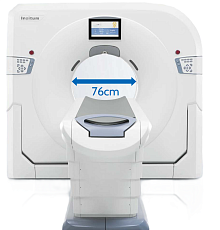

Компьютерный томограф

Компьютерный томографSinoVision Insitum 16/32

- Количество физических срезов: 16/32

- Минимальная толщина среза: 0,625 мм

- Мин. время оборота рентгеновской трубки: 0,5 с.

- Диаметр апертуры гентри: 76 см